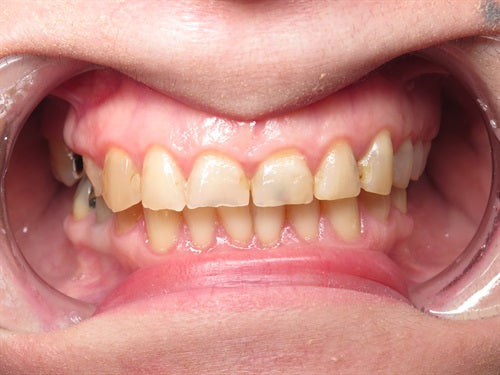

Dahl technique Doc Terry style by Dr. Ahmad Fayad

Introduction: 40 year old female on a tight budget and is slowly losing her teeth. She was referred to me by another patient who had the same style buildups. Decided... Read More